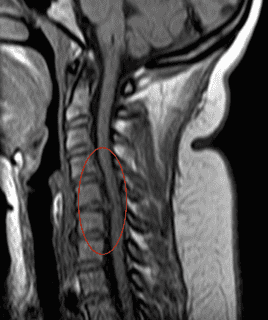

-Случай Nº 17635

Грыжа или протрузия межпозвоночного диска на уровне шейного отдела может задеть нервные корешки или спинной мозг. В этом отделе позвоночника очень мало свободного пространства для дисков, отсюда более частое возникновение грыж с компрессией нервных корешков или спинного мозга.

Если есть подозрение на повреждение нервного корешка, проводится магнитно-резонансная томография (МРТ) или компьютерная томография (КТ). Если речь идет о грыже диска или стенозе позвоночного канала, решение о лечении основывается на клинических данных и на осмотре пациента.